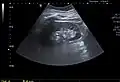

The complex cyst can be further evaluated with doppler ultrasonography, and for Bosniak classification and follow-up of complex cysts, either contrast-enhanced ultrasound (CEUS) or contrast CT is used.[13]

-

Renal cyst as seen on abdominal ultrasound -